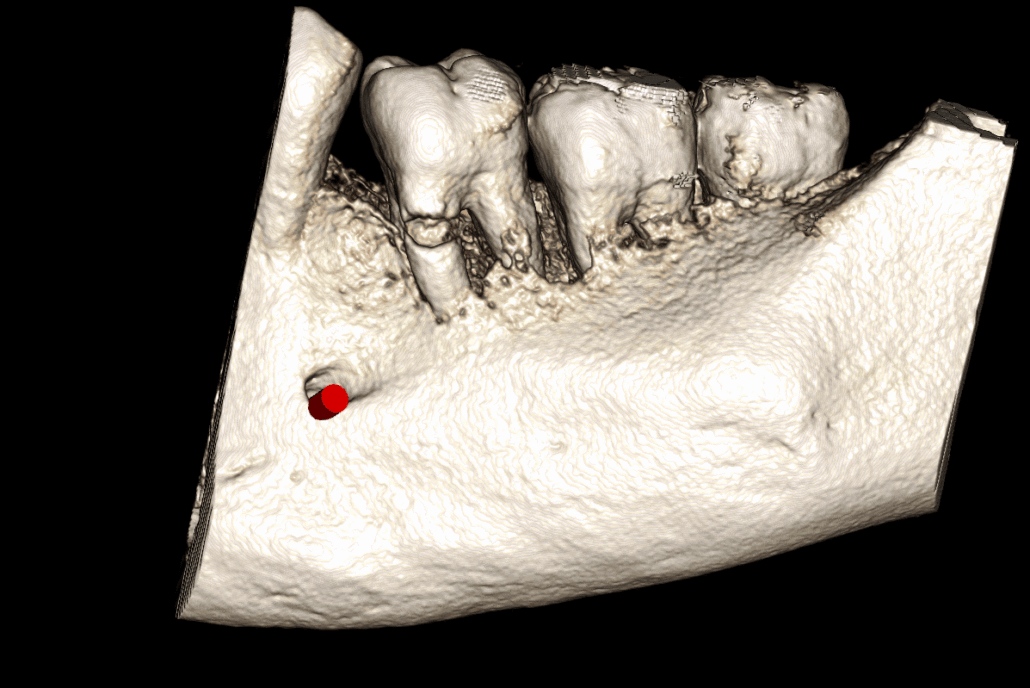

LL678

The LL6 mesial-buccal root demonstrates a large root resorption in the cervical third with a wide area of root perforation. There is also another small mesial external resorption.

The LL6 also has periradicular radiolucencies indicating a combined endo-perio lesion. It is most likely unrestorable and has poor prognosis. The inferior dental canal does not contact the LL6 roots.

The LL8 roots have a marked distal dilaceration/apical hooks. The upper border of the inferior dental canal contacts the inferior surface of the LL8 roots.

Image 2